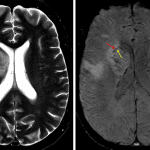

MRI

- Multifocal areas of parenchymal restricted diffusion involving the bilateral cerebral and cerebellar hemispheres

- The largest lesion is located in the anterior right basal ganglia/anterior limb of the right internal capsule, which measures 3 x 2.5 x 2.3 cm, demonstrates peripheral enhancement which is incomplete along its ependymal margin, and demonstrates central restricted diffusion

- Linear enhancement extends along the superior margin of the right lateral ventricle

- Many of these lesions demonstrate peripheral susceptibility artifact

- Surrounding vasogenic edema, particularly involving the right basal ganglia and right frontal subcortical lesions